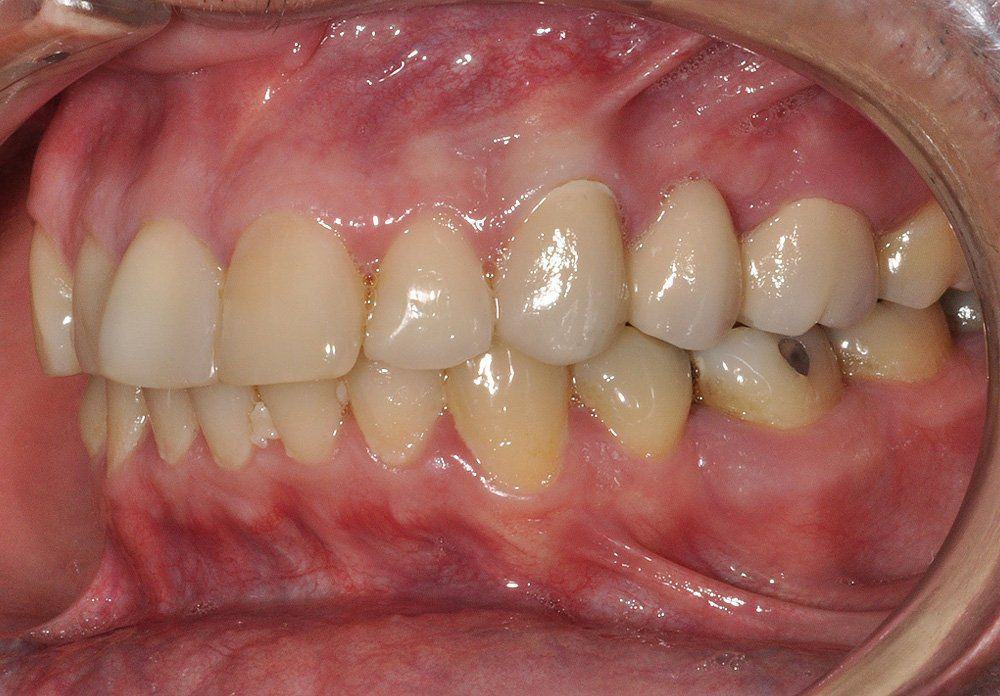

Reporte del Caso: Paciente sexo masculino, 36 años, con diagnóstico de esquizofrenia y trastorno bipolar en tratamiento. Consulta por el recambio de dos prótesis fijas plurales (PFP) de reemplazo de dientes 4 y 13 con pilares en piezas 3, 5, 12 y 14 mediante rehabilitaciones unitarias de los dientes pilares y reemplazo mediante implantes en zonas edéntulas.

El estudio imagenológico evidencia una pérdida ósea severa en altitud y grosor, situación que complejiza la colocación de un implante. Se analizan alternativas de tratamiento y se opta por una vestibuloplastía mediante autoinjerto conectivo de mucosa palatina que se reposiciona sobre la zona del defecto óseo. Además se realiza retratamiento de ambas PFP, ahora en zirconia, por motivos estéticos y oclusales. Se realizan controles posteriores para evaluar la respuesta gingival a la vestibuloplastía.